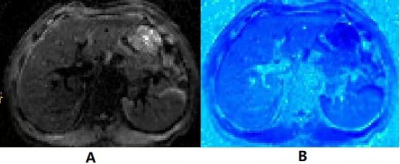

The representative sADC map and DW MRI–based elastography were shown in Fig.1. The median values of µDiff for significant fibrosis (S≥2) were 5.305kp, and for advanced fibrosis (S≥3) were 5.380kp, respectively. The µDiff showed a significant correlation with liver fibrosis stage (rho=0.55, P<0.001). The ROC curves of µDiff for the diagnosis of significant fibrosis and advanced fibrosis are shown in the Fig. 2, and the areas under the curves were 0.864 and 0.821, with cutoff of >4.515kp and >4.945kp, respectively.

Fig 1.The representative shifted apparent diffusion coefficient map (A) and DW MRI–based elastography (B).